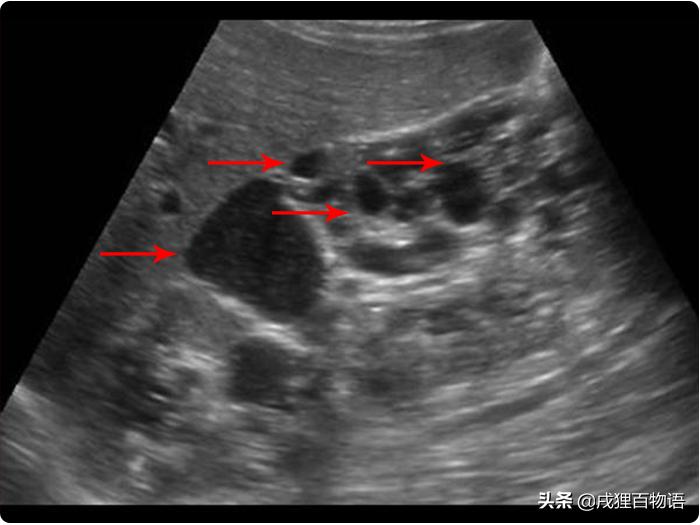

1 B超

诊断多囊肾,用B超检查最快捷。

任何事物都不会完美,B超的局限在于没法查出过小“水泡”。在出生之时,肾脏中的水泡可能只有1mm或者更小,在大小超过2mm之前,一般是难以察觉的。用B超检测多囊肾最好等猫咪9-10个月之后,这时候的准确度大致能达到91-98%。